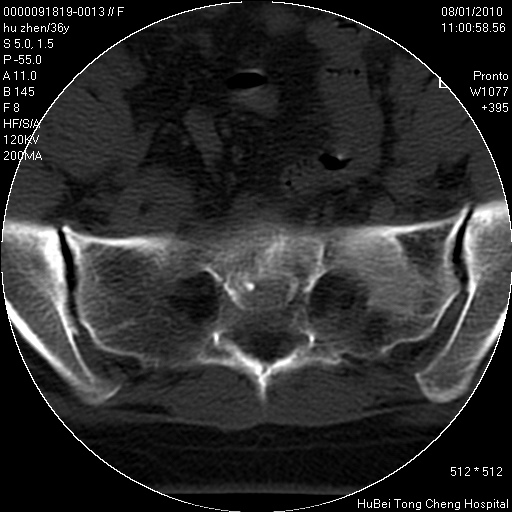

患者 女,36岁。右侧腰腿痛半月余。腰骶椎mr平扫偶然发现骶椎异常信号。

临床诊断:1)腰椎间盘突出症。2)骶椎肿瘤性病变?

骶椎ct平扫(层厚、层距均为5mm),图像如下:

考虑s1骨纤维异常增殖症。